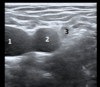

left is lateral, medial is right what are these things (worksheet 4)

1. brachial plexus trunks 2. SCM 3. carotid artery (left)